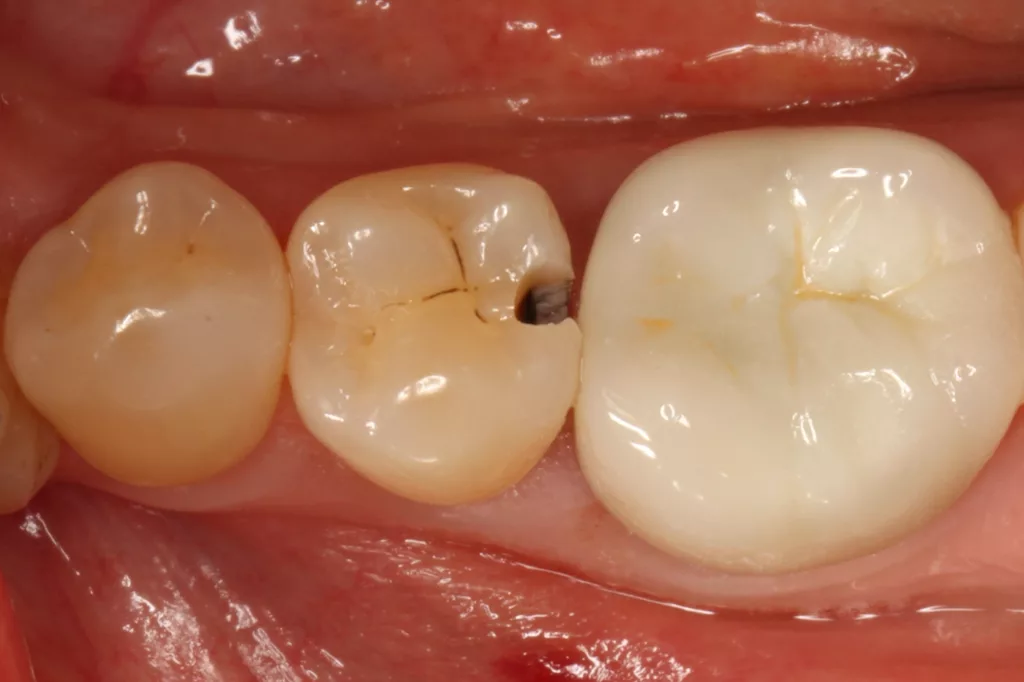

Fall 5: Versorgung einer okklusalen Kavität an einem unteren Molaren

Auch im Molarenbereich können Bulkflow-Materialien effektiv und ökonomisch eingesetzt werden, ohne Abstriche an der Ästhetik machen zu müssen, was der Fall des hier versorgten Zahnes 46 bei einer 22-jährigen Patientin zeigt. Die Abbildung 24 stellt die bereits präparierte und mit einem Einzelzahnkofferdam isolierte Kavität mit der Phosphorsäurekonditionierung der Schmelzränder (Gel Etchant, Kerr) dar. Die Entscheidung zur absoluten Trockenlegung fiel aufgrund der nicht so einfach kontrollierbaren Zunge und der vielen Schluckreflexe, was das Risiko einer ungewollten Speichelkontamination der Klebefläche unverhältnismäßig erhöhte.

Die Verwendung des Kofferdams ist generell eine sehr empfehlenswerte, aber keine zwingende Voraussetzung zur Etablierung einer suffizienten Kontaminationskontrolle [47,96]. Das bisher auch bereits verwendete Zwei-Schritt-Universaladhäsiv G2 Universal wurde hier in der selektiven Schmelzätztechnik angewendet, d.h., das Material arbeitet auf dem Dentin selbstkonditionierend (Abb. 25). Die bislang zu diesem innovativen Mehrflaschen-Universaladhäsiv publizierten Daten zeigen eine beeindruckende Performance, die den Vergleich mit sogenannten Goldstandards [98] wie einem Optibond FL nicht scheuen müssen [13,18,34,58,63,114,119,127,130]. Im nächsten Schritt wurden die einzelnen Höcker mit dem angenehm standfesten Flowable aufgebaut (Abb. 26). Die Abbildung 27 zeigt die komplett versorgte okklusale Kavität, die Abbildung 28 die Situation unmittelbar nach Ausarbeitung und Politur. Erneut beeindruckt die gute Farbadaptation.